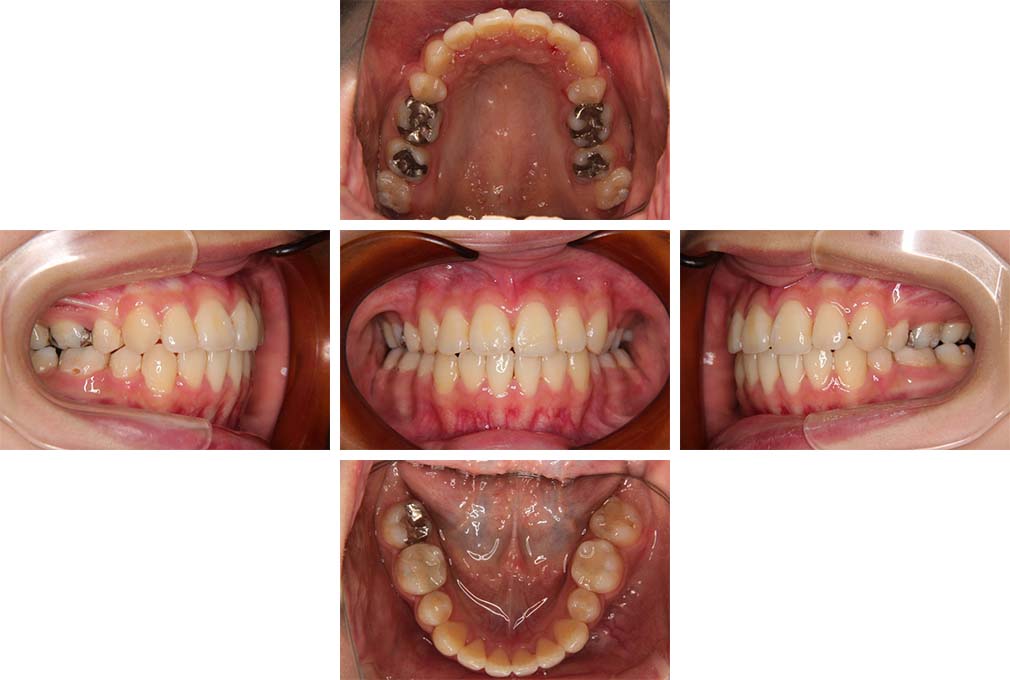

CASE:04

アングルⅢ級傾向を持つ叢生

初診時年齢 22歳

性別 女性

治療費の目安 105万円程度(治療開始時)

上顎右側犬歯が唇側に転位していることを主訴に県内歯科医院から紹介来院された。骨格的にはⅢ級傾向で上顎右側犬歯が唇側転位となり、側切歯が口蓋側に転位していた。下顎前歯が叢生になっていることも相まって上下の正中線は右側に大きくずれていた。アングルⅢ級傾向を持つ上下顎前歯部叢生と診断した。

上下顎小臼歯を抜歯していただき上顎舌側、下顎唇側マルチブラケット装置を使用して動的治療を行った。矯正用ゴムの使用など協力状態も良く、正中線の大きな移動があったのも関わらず2年10カ月で装置を撤去し保定へ移行した。保定移行後14年が経過し、ご息女の診察でご来院いただいていたことから、口腔内を拝見したが、下顎前歯のわずかなずれがあったものの大きな歯列の乱れはなく歯列は安定していた。動的治療期間2年10カ月間。

治療前

22歳6か月

治療後

動的治療期間2年10カ月間

25歳6か月

治療終了

動的治療終了後2年2カ月

28歳8か月

14年経過

動的治療終了後14年7カ月

40歳1か月